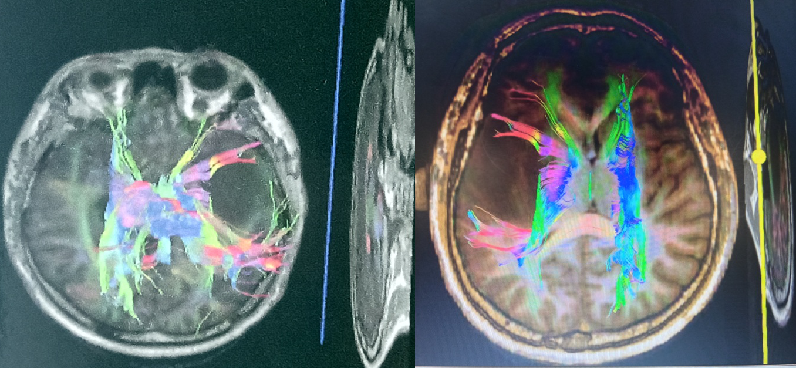

最大范围安全切除肿瘤是胶质瘤首选治疗策略,手术切除程度是患者术后总生存期的孤立影响因素。

(术前多模态影像融合检查)

(术前神经导航定位)